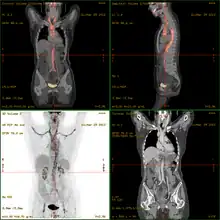

- 18F-fluorodeoxyglucose positron emission tomography/computed tomography (FDG-PET/CT)has become a widely used imaging tool in patients with suspected Large Vessel Vasculitis, due to the enhanced glucose metabolism of inflamed vessel walls.[16] The combined evaluation of the intensity and the extension of FDG vessel uptake at diagnosis can predict the clinical course of the disease, separating patients with favourable or complicated progress.[17]